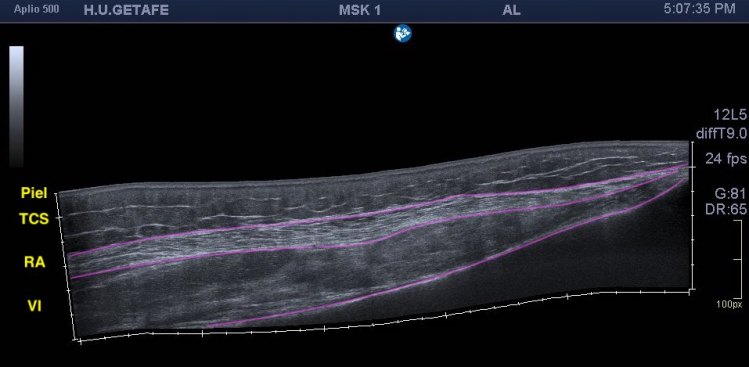

Un breve recuerdo anatómico de la zona tanto en eje largo como en eje corto (longitudinal o transverso), fig 3 y 2 respectivamente, . Fíjese la/el lectora en el posicionamiento del pictograma de referencia.

Repasamos anatomía y aprender una forma de estudio de la inserción del tendón del recto anterior del cuadricipital donde vas a ver esas fibras, perfectas. Como se tiene que ver para buscar entensopatías a ese nivel y para que las reconozcas en otras localizaciones típicas, aquiles, epicóndilo…etc…

Explorar esta zona de inserción es complejo, el recto anterior, que luego es el tendón intramuscular o rafe del recto anterior del cuadriceps, inserta mediante su tendón buscando la profundidad en la cadera, con lo que encontramos anisotropía…te voy a enseñar una forma de explorarlo donde vas a poder corregir esa anisotropía. La exploración habitual es con la pierna en extensión y decúbito supino, pero vamos a pedir al paciente que se siente en la camilla, baje la pierna y apoye el talón del pie, el tronco del paciente mínimamente inclinado hacia atrás, la cadera y la rodilla en extensión y la sonda colocada en la zona de inserción…la imagen que logras es esta maravilla, imagen 3.

Es importante que conozcas la zona, la anatomía, y que pruebes la proyección que te he explicado, verás esas fibras insercionales muy bien porque corriges la anisotropía.